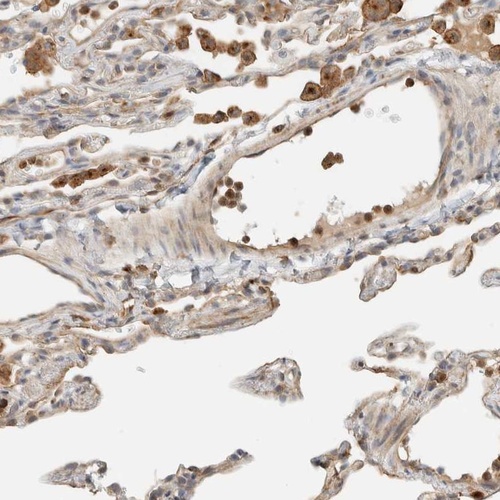

Immunohistochemistry analysis in human lung and skeletal muscle tissues using Anti-RAB11FIP1 antibody. Corresponding RAB11FIP1 RNA-seq data are presented for the same tissues.